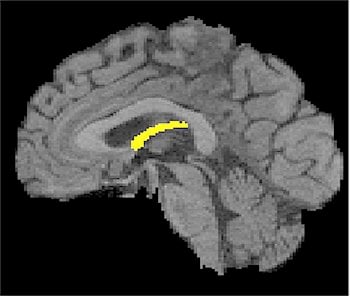

The degeneration of a small, wishbone-shaped structure deep inside the brain may provide the earliest clues to future cognitive decline, long before healthy older people exhibit clinical symptoms of memory loss or dementia, a study by researchers with the UC Davis Alzheimer’s Disease Center has found.

The longitudinal study found that the only discernible brain differences between normal people who later developed cognitive impairment and those who did not were changes in their fornix, an organ that carries messages to and from the hippocampus, and that has long been known to play a role in memory.

Hippocampal atrophy occurs in the later stages of cognitive decline and is one of the most studied changes associated with the Alzheimer’s disease process. However, changes to the fornix and other regions of the brain structurally connected to the hippocampus have not been as closely examined. The study found that degeneration of the fornix in relation to cognition was detectable even earlier than changes in the hippocampus.

Image Source: The image highlighting the location of the fornix is adapted from the UC Davis press release.